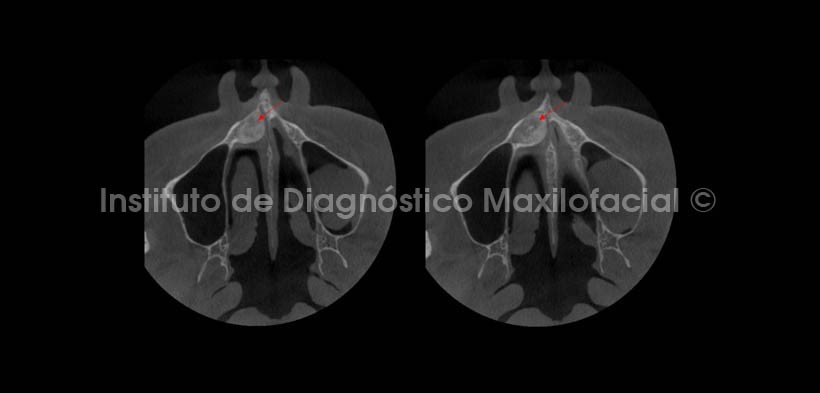

Se realizaron cortes multiplanares; en los cuales se observa el leve estrechamiento del conducto nasopalatino en su porción más superior en el corte coronal (Fig. 3), además del mencionado desplazamiento cefálico del piso de fosa nasal del lado derecho. En cortes axiales (Fig. 4), se aprecia el ocupamiento de la parte anterior de la fosa nasal derecha condicionado por el crecimiento de la lesión, observando la cercanía de esta con la espina nasal anterior, y en cortes sagitales (Fig. 5) se evidencia un leve desplazamiento de la tabla ósea vestibular.